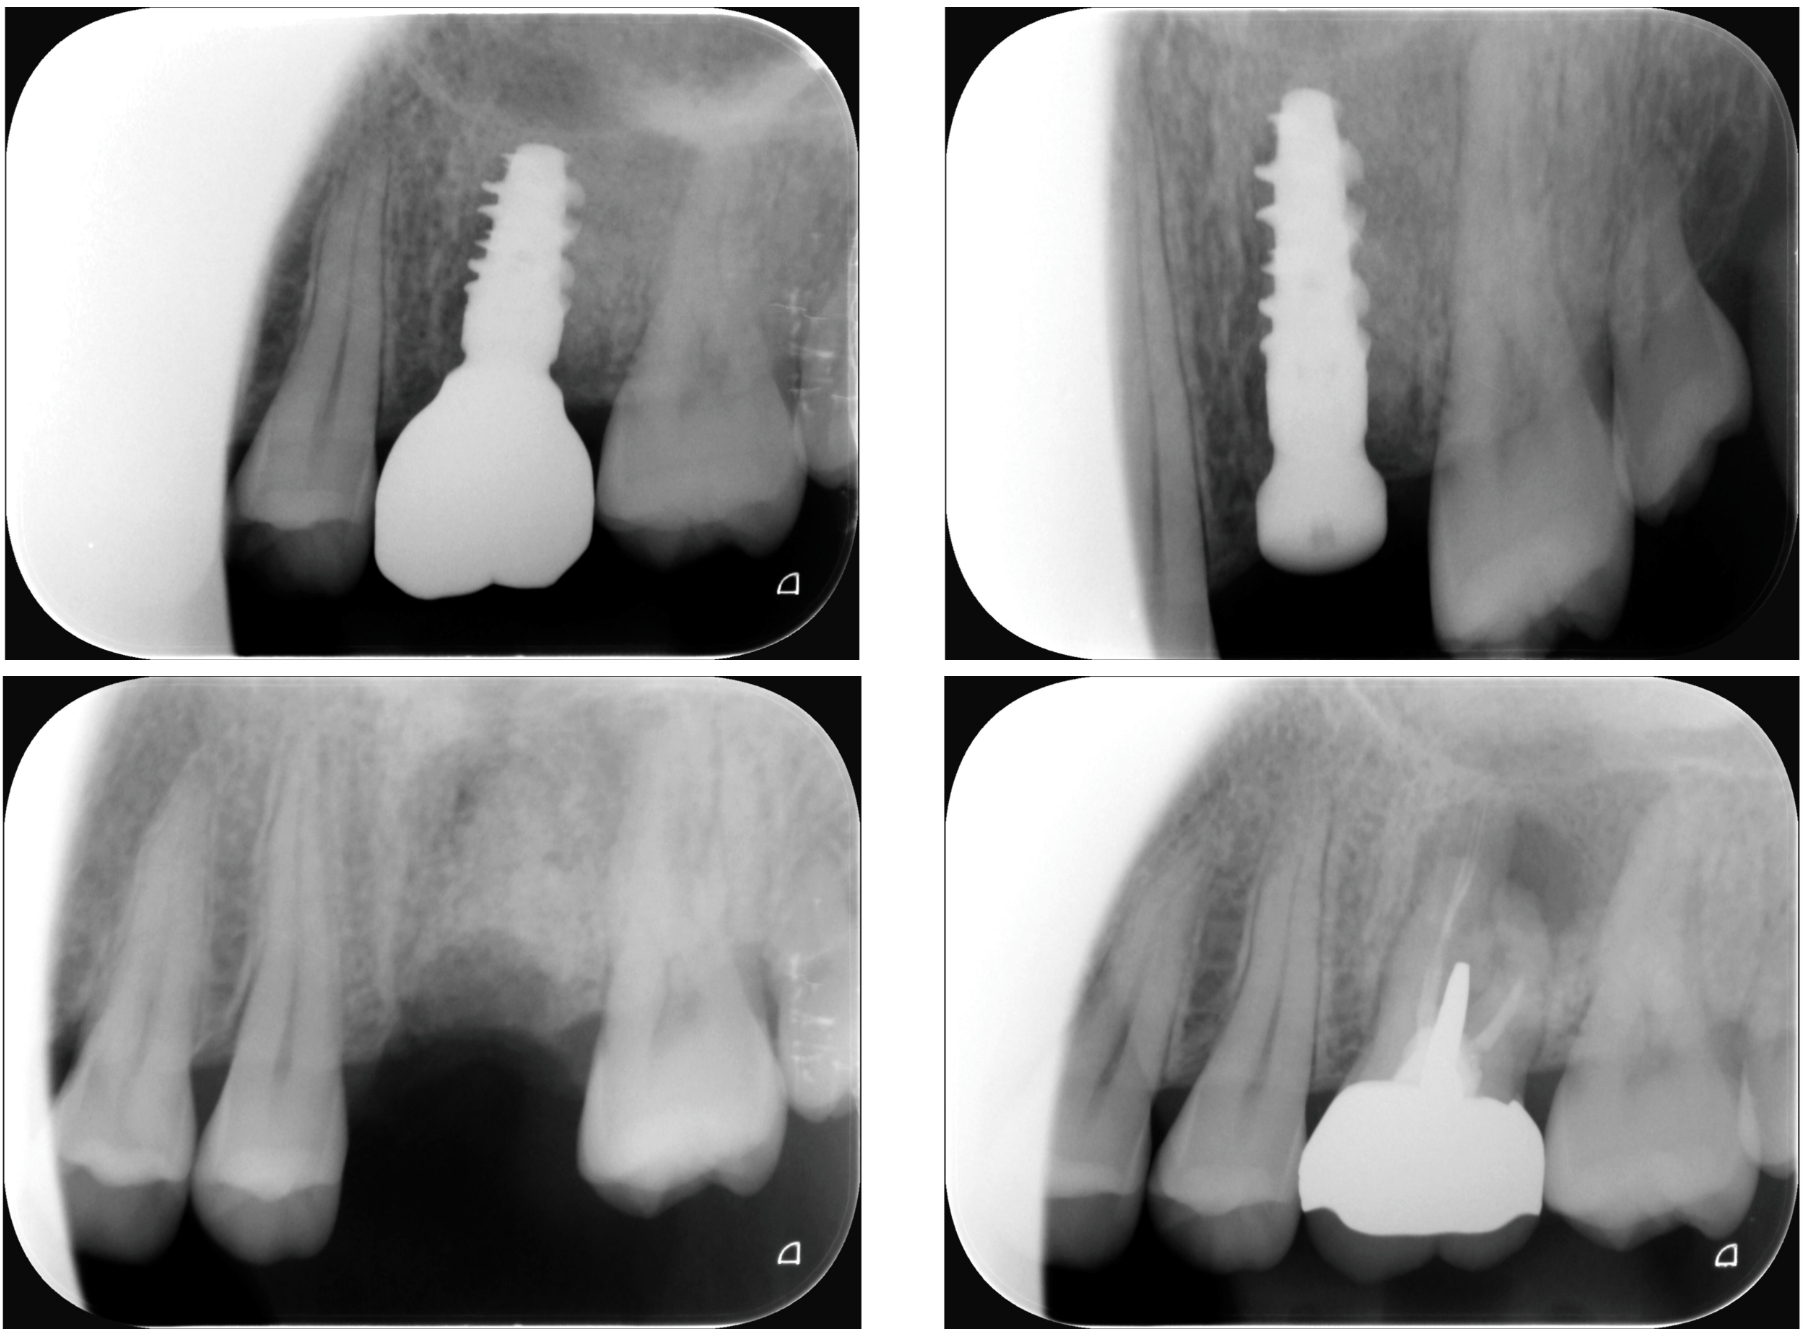

Dental implants are one of the most advanced solutions for replacing missing teeth—designed to restore not just your smile, but also your ability to chew, speak, and live confidently. A dental implant acts as a new tooth root, made from titanium and placed into the jawbone. It supports a crown or bridge, creating a replacement tooth that looks, feels, and functions like a natural one.

A dental implant consists of three main parts:

- Implant fixture – a titanium root placed into the bone

- Abutment – a connector between implant and crown

- Crown – the visible tooth, custom-designed for aesthetics and function

The result is a stable, long-term tooth replacement that integrates with your body through a biological process called osseointegration.

Front Teeth vs. Back Teeth Implants

Back Teeth (Molars)

- Focus on strength and load-bearing

- Larger implants are often used

Front Teeth

- Focus on aesthetics and gum contour

- Requires precise, prosthetic-driven planning

3. Implant Placement

Titanium implant is placed into bone → healing phase (2–3 months).